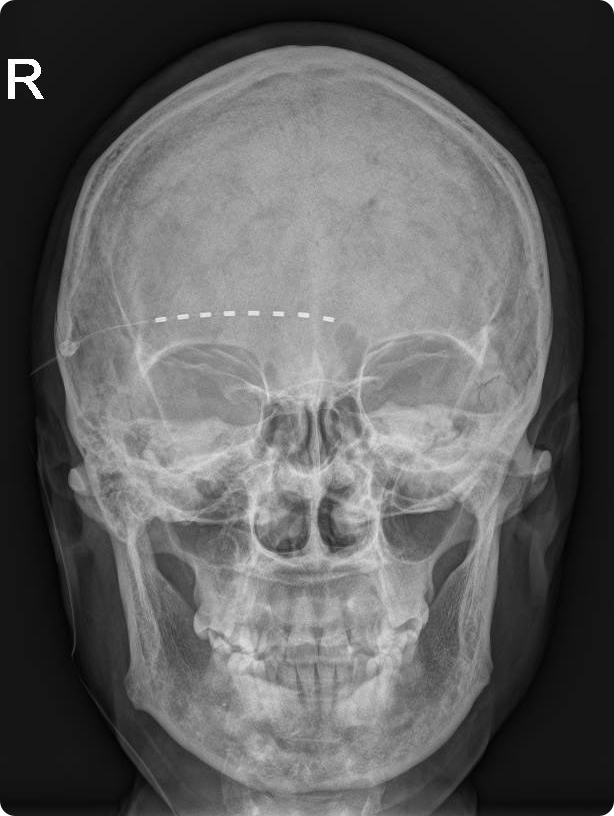

基本信息:患者,女性,53岁,已婚。 主诉:右侧额面部疼痛1周,疱疹1天。 现病史:患者自诉1周前运动后出现右侧额面部疼痛,呈持续性疼痛,并向额顶部放射,不伴恶心、头晕,不伴畏寒、发热,不伴黑矇。1天前疼痛处出现红色皮疹,呈簇状分布,疼痛加重,呈针刺样、烧灼样痛,并出现爆发性疼痛,间隔20min-1h剧痛一次,爆发时持续约60s-120s,视觉模拟评分法(VAS)评分8-10分,严重影响夜间睡眠、日常食欲,为求进一步诊治,遂来我院疼痛科门诊就诊,以“疱疹后三叉神经痛”收入院。起病以来,精神饮食不佳,睡眠差,体重无明显改变,体力下降,二便无异常。 既往史:无特殊。 婚育史:已婚,配偶体健,育有一子,身体健康。 家族史:否认家族中遗传疾病史或其他神经系统疾病史。 辅助检查:暂无。 体格检查:体温:36.6℃,脉搏:72次/分,呼吸:16次/分,血压:107/66 mmHg。发育良好,营养良好,痛苦面容,查体合作,正力体型,步态正常,自主体位,神志清楚。 专科查体:右侧额面部可见多发簇状红色皮疹,皮疹主要沿三叉神经眼支的支配区域分布,上延伸至额顶部,下延伸至下眼睑,中心无结痂,周围有红晕,无溃破,局部皮肤轻触痛(+),皮肤浅感觉减退,四肢肌力及浅感觉正常,生理反射存在,病理反射未引出。 初步诊断:疱疹后三叉神经痛、带状疱疹性神经痛 鉴别诊断: 单纯疱疹:单纯疱疹表现有散在的疱疹分布,但无规律性,且不伴有疼痛。本病例疼痛剧烈,伴有皮肤轻触痛,可排除。 治疗经过: 2025年10月26日: 入院后完善血生化、心电图、颅脑磁共振成像(MRI)等相关检查,未见明显异常。入院后治疗方案: ①抗病毒:溴夫定125mg qd口服;②皮肤疱疹区域对症处理:阿昔洛韦乳膏、炉甘石洗剂局部涂擦,以及高能量激光等物理治疗;③镇痛:依托考昔60mg qd 口服,普瑞巴林150mg bid 口服,盐酸曲马多100mg prn肌肉注射;④营养神经:甲钴胺500ug +维生素B1 100mg tiw 肌肉注射;⑤改善睡眠:酒石酸唑吡坦10mg qn口服等。 2025年10月28日: 治疗2日后,患者爆发痛间隔20min-1h, VAS 9-10分,疼痛未明显缓解。调整治疗方案: 停用普瑞巴林,换用苯磺酸克利加巴林20mg bid,其余治疗方案不变,治疗3天后爆发痛间隔30min-2h,VAS 7-8分,疼痛有所缓解。 2025年11月03日: 超声引导下行右眶上神经诊断性阻滞,2h内无爆发痛发作。 2025年11月04日: 超声引导下行右侧眶上神经脉冲射频术;术后疼痛较前减弱,爆发痛间隔时间延缓至2h-4h,VAS 6-7分。 2025年11月08日-11日: 患者疼痛加重,爆发痛间隔时间30min-1h,VAS 7-8分,调整苯磺酸克利加巴林40mg bid。治疗3天后,爆发痛间隔时间4h左右,VAS 6-7分。 2025年11月16日: 数字减影血管造影(DSA)引导下行短时程右眶上神经电刺激置入术,置入后10天拔出电极导线。VAS 3-4分,无爆发痛。出院前嘱咐继续口服苯磺酸克利加巴林40mg bid,嘱1月后复诊,依据疼痛缓解情况,调整苯磺酸克利加巴林剂量。 随访:出院1月后患者门诊复诊疼痛缓解满意,VAS 2分,无明显不良反应,睡眠与精神状态良好,嘱患者逐渐减少苯磺酸克利加巴林剂量(40mg bid 至 20mg bid),一月后继续随诊。 图1:电刺激电极置入术后